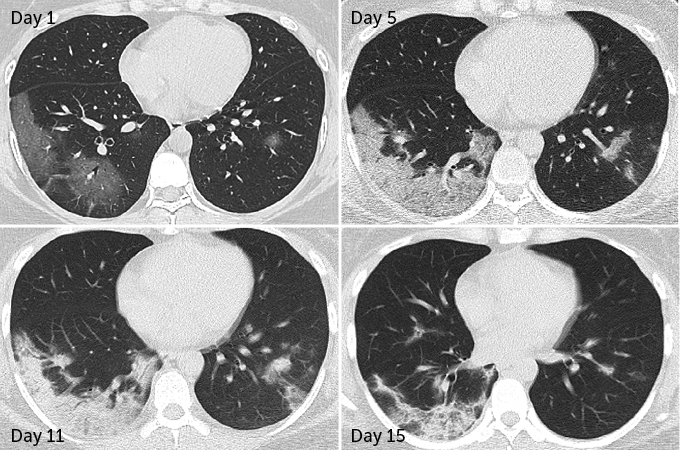

Patchy spots often show up in lung scans of actively sick COVID-19 patients (colorized scan shown). Some lung damage could be long-lasting, new research suggests.

In 70 patients who survived COVID-19 pneumonia, 66 had some level of lung damage visible in CT scans taken before hospital discharge, researchers report March 19 in Radiology. The damage ranged from dense clumps of hardened tissue blocking blood vessels within the tiny air sacs called alveoli, which absorb oxygen, to tissue lesions around the alveoli, Yuhui Wang, a radiologist at Huazhong University of Science and Technology in Wuhan, China, and colleagues found.

But while initial lung images indicate that SARS and MERS typically set into just one lung, COVID-19 appears to be more likely to afflict both lungs right away. In 75 of the 90 patients admitted to Huazhong University Hospital with COVID-19 pneumonia from January 16 to February 17, damage was seen across both lungs, Wang and colleagues report. CT scans taken before hospital discharge revealed that 42 out of 70 patients displayed the type of lesions around the alveoli that are more likely to develop into scars.